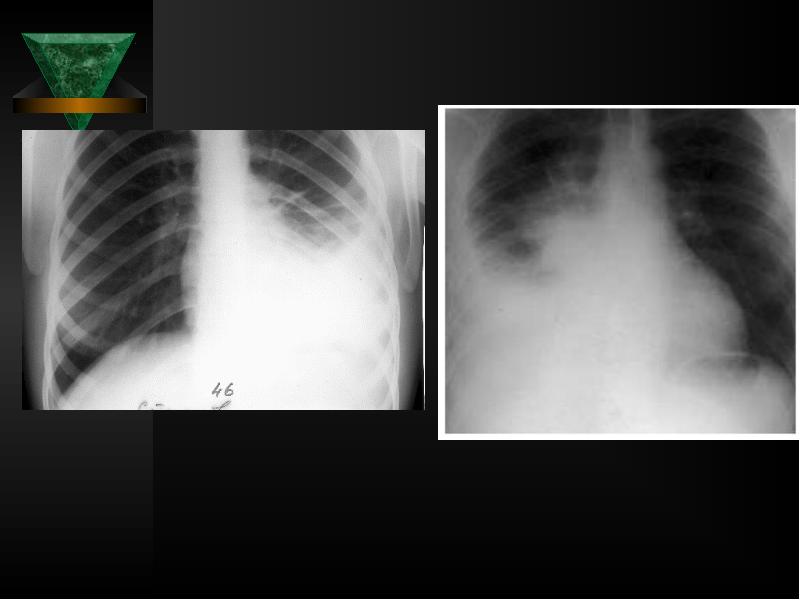

- 40. Рентгенологическое исследование легких Чаще всего при свободном выпоте в плевральной

- 42. Рентгенологическое исследование легких следует производить до и после эвакуации выпота из

- 43. При выпотах небольшого объема затемнение может занимать лишь реберно-диафрагмальный синус, при